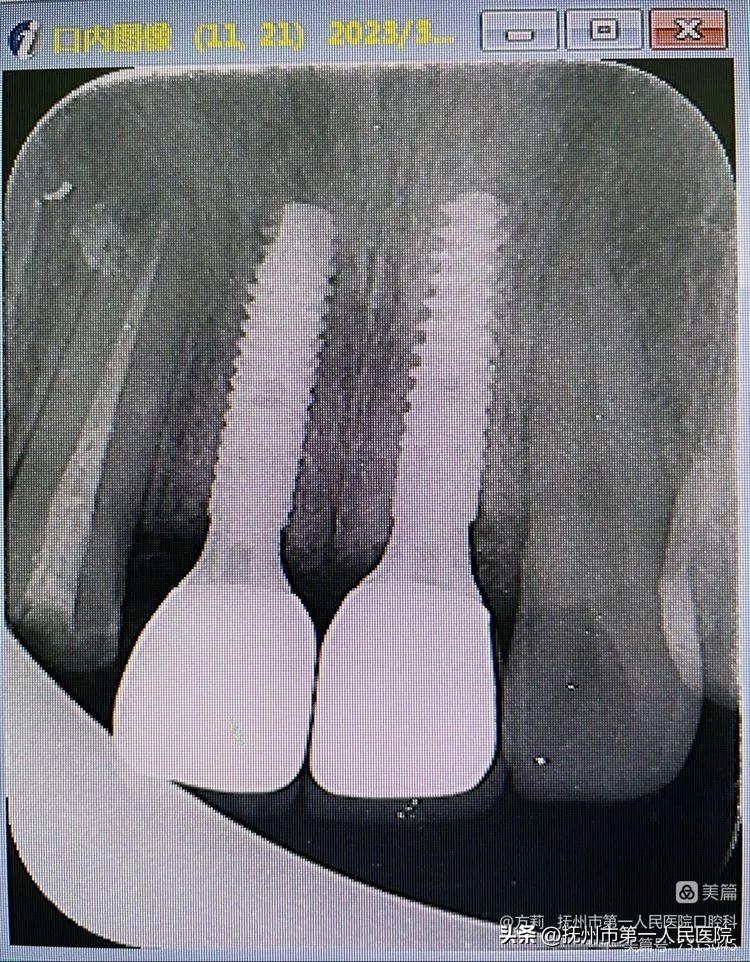

患者术后20个月根尖片影像显示:11、21无明显骨嵴吸收!

戴牙术后影像显示:基台与植体之间,牙冠与基台之间均衔接紧密,完全就位!